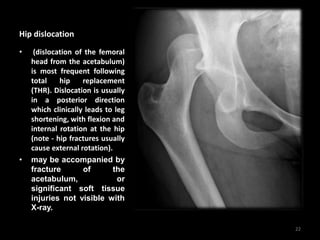

Hip dislocation

• (dislocation of the femoral

head from the acetabulum)

is most frequent following

total hip replacement

(THR). Dislocation is usually

in a posterior direction

which clinically leads to leg

shortening, with flexion and

internal rotation at the hip

(note - hip fractures usually

cause external rotation).

• may be accompanied by

fracture of the

acetabulum, or

significant soft tissue

injuries not visible with

X-ray.

• The femoral head

lies superior and

lateral to the

acetabulum

• No associated

fracture is visible in

this case but

significant soft

tissue injury is likely